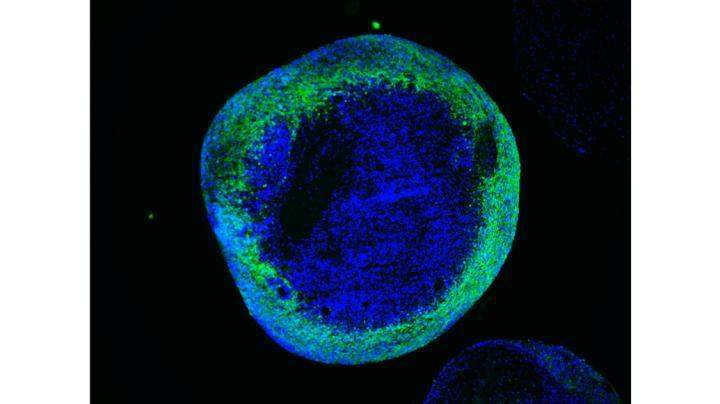

为了实现这一目标,作者采用了细胞重编程技术,该技术能够将皮肤中的细胞转化为能够产生神经元的干细胞。然后,他们使用分子剪刀CRISPR / Cas9精确地从患者细胞中去除了突变,并将突变引入到对照细胞中。因此,作者能够在受控遗传背景下研究SURF1突变的特异性作用。接下来,它们产生了具有三维结构的神经元和大脑类器官,并再现了人类早期大脑发育的特征。

使用这些模型,作者发现患者中看到的神经元缺陷可能是由神经前体(即生成神经元的细胞)水平上出现的能量不足引起的。这些能量缺陷会导致神经元分支不足,从而导致发育过程中大脑功能不正常。最后,作者证明可以通过使用SURF1基因替代疗法改善祖细胞的能量输出或使用目前对儿童临床使用安全的药物Bezafibrate来纠正神经元分支缺陷。